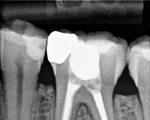

Endodontics or root canal treatment is a dental procedure to fix a tooth that cannot be filled or restored any other way. If the tooth is severely decayed into the pulp of the tooth and / or infected, root canal treatment is usually the only option to save the tooth.